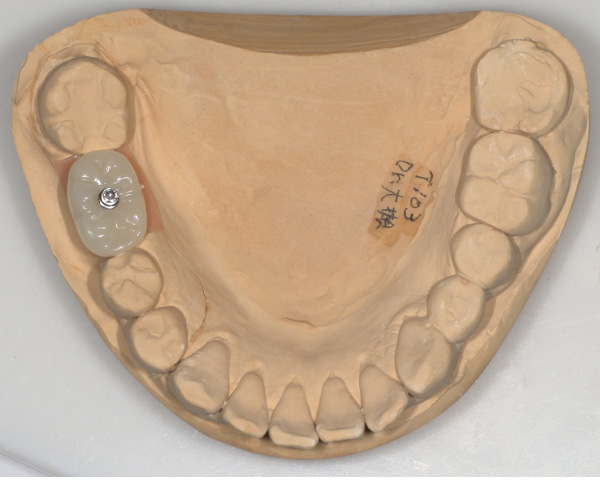

骨移植(人工骨+メッシュプレート)を行い、骨を造りました。

CT画像 -

インプラント手術を行いました。

手術の時に使用するサージカルステント